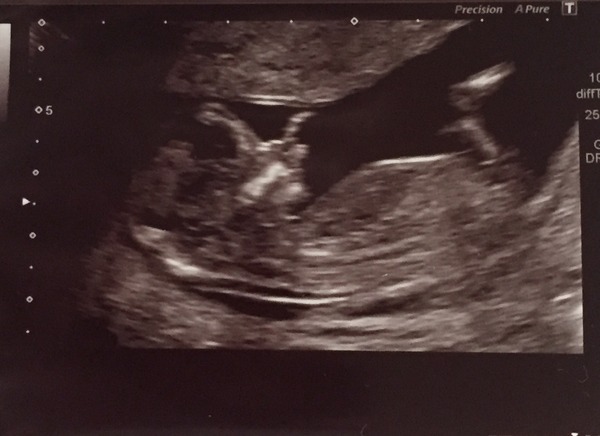

Scan went well. We have been dated 29th June. So happy. It all feels more real now. I could have lay watching my little munchkin on that screen all day, so special Smile

Glad your scan went well too, Miracles. I had mine at 9am this morning and it, too, went well :)

So relieved. Was expecting to see five arms and one leg, knowing me and my luck ha ha! Everything looks fine. My date is still 30 June so I just qualify for this thread :)